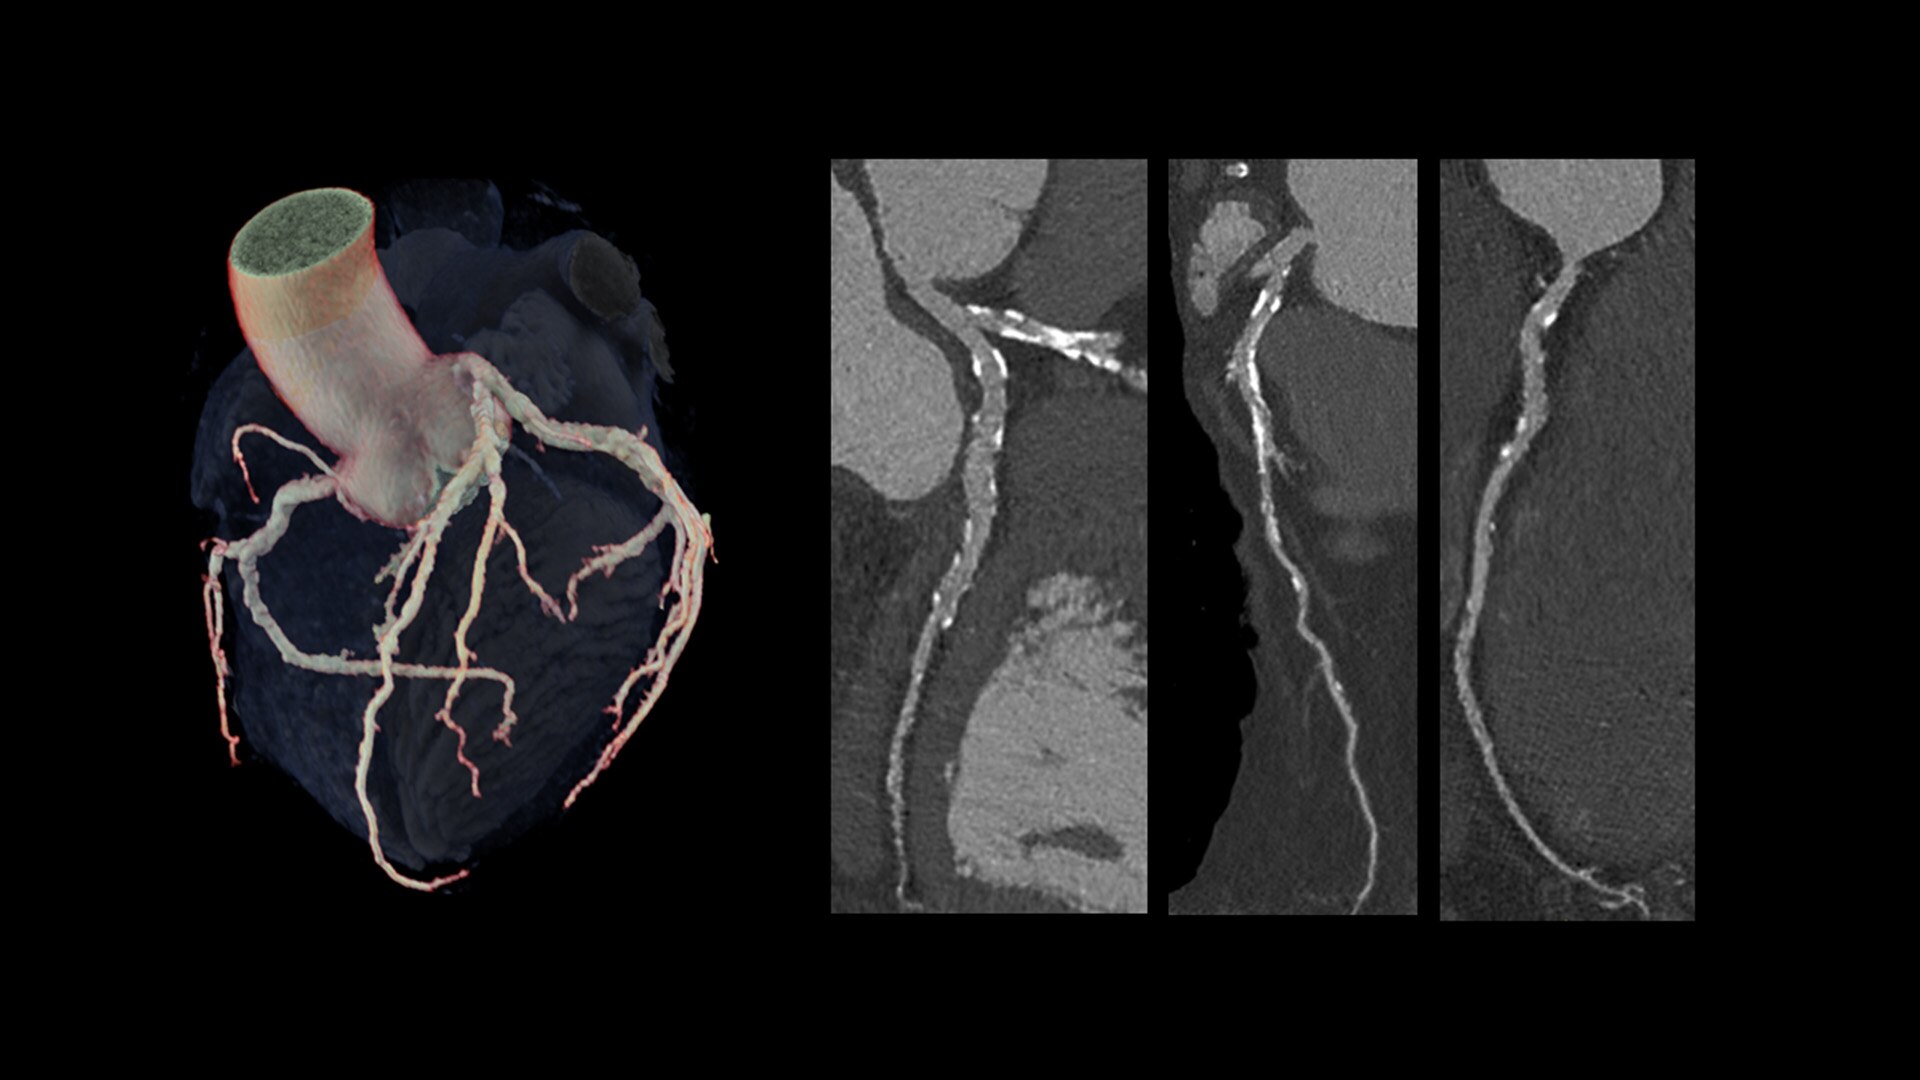

Cardiac CT has become a front-line, non-invasive imaging tool for diagnosing, treatment planning and monitoring of cardiovascular disease

Healthcare providers are striving to improve patient health but are struggling with increasingly complex exams, insufficient or inexperienced staff, and operational and capital efficiency. Revolution™ Vibe, designed to deliver leading-edge technology, features advanced cardiovascular capability. It improves patient access and operational efficiency, prioritizes patient care and supports your facility's growth with lower lifecycle costs.

Unlimited 1-Beat Cardiac is designed to provide consistent, high-quality imaging for accurate diagnoses, even in challenging patients with atrial fibrillation, breath-holding difficulties, heavily calcified coronaries, in-stent restenosis, and situations where an ECG trace is unavailable.